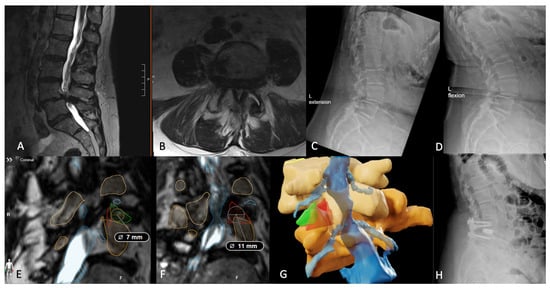

- Tabarestani, T.Q.; Sykes, D.A.W.; Kouam, R.W.; Salven, D.S.; Wang, T.Y.; Mehta, V.A.; Shaffrey, C.I.; Wiggins, W.F.; Chi, J.H.; Abd-El-Barr, M.M. Novel Approach to Percutaneous Lumbar Surgeries via Kambin’s Triangle-Radiographic and Surgical Planning Analysis with Nerve Segmentation Technology. World Neurosurg. 2023, 177, e385–e396. [Google Scholar] [CrossRef] [PubMed]